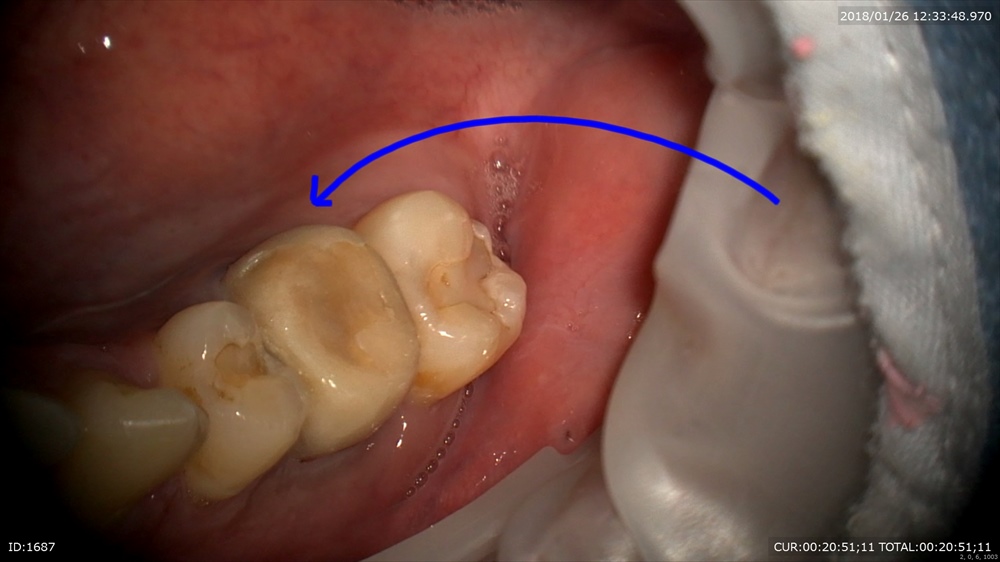

最後は精密根管治療 11月。はこの方重症のむし歯で歯茎がはれてます。

本日 きえたー。嬉しい!

比較